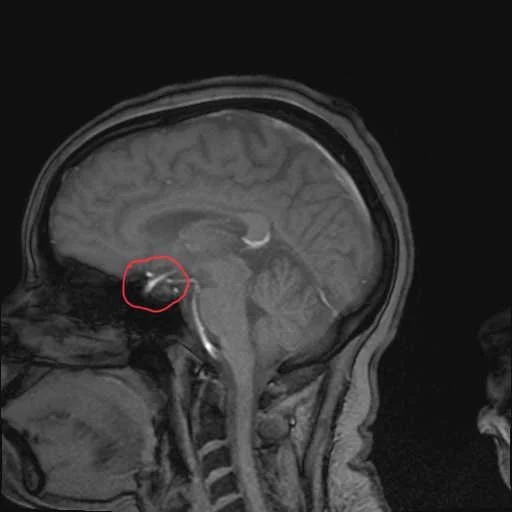

On September 1st my endocrinologist informed me that there is a 7mm tumor on my pituitary gland which was causing my symptoms. Now what’s next…you guessed it. More lab results!!! My endocrinologist ordered more blood work, a 24-hour urine test, and a 3-day saliva test. Now my next appointment wasn’t until October 6th but I kept calling to see if there were any cancellations and lucky enough there was one. I got my appointment moved up to September 16th (yaaaaay)!

On September 28th I had my appointment with Dr. Andrew Little, Chief, Skull Base Surgery Neurosurgeon at Barrow Neurological Institute, and discovered a little more about my tumor. My little friend is wrapped around my ophthalmic artery (yikes). The doctor mentioned since it’s wrapped he will need assistance from an ENT (ears, nose, & throat doctor) and they will try their best to get all of it but if not I will have to be on medication or do radiation. Also, that I’ll be in the hospital for 2 days and will probably have to take 3 weeks off from work.

The surgery lasted about 3 hours. Oh, I mentioned earlier that my tumor was wrapped around my ophthalmic artery and they had to be very careful but I didn’t mention that if the artery was touched the wrong way it could cause a stroke or death 😅. Well, guess what, they got ALLL of the tumor so no radiation 🙌🏾!! They also got the ring off without breaking it! After surgery, I woke up very alert which surprised everyone and moved to the ICU to monitor my cortisol levels to make sure since the tumor was removed my levels will decrease.